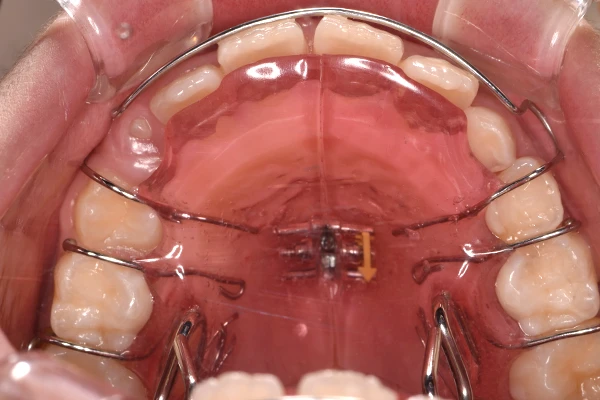

反対咬合

| 診断名・主訴 | 前歯反対咬合 |

|---|---|

| 年齢・性別 | 12歳・男性 |

| 治療期間・回数 | 1年半 18回 |

| 治療に用いた主な装置 | リンガルアーチ(前方誘導弾線) |

| 抜歯部位 | なし |

| 治療費 | 35万円(税抜) |

| リスク・副作用 | 装置による違和感・疼痛・歯肉退縮・歯根吸収・虫歯のリスクなど |

治療前

治療中

治療後